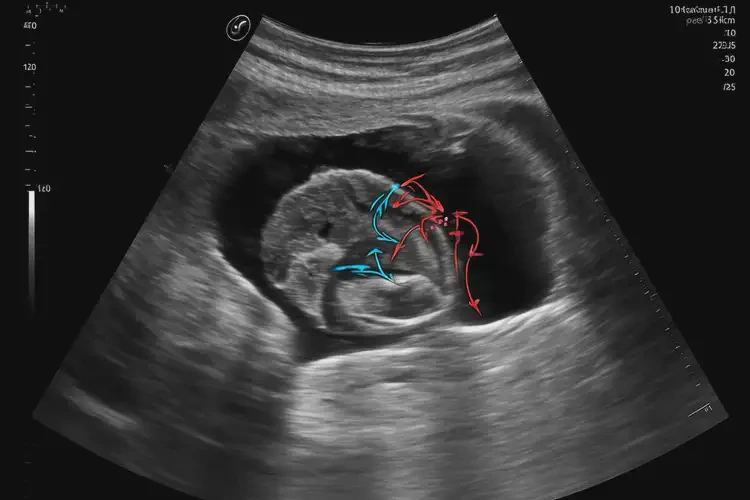

孕10周4天胎心160寶寶還能要嗎

胎心160次/分鐘在孕10周4天屬于正常范圍,寶寶可以繼續(xù)妊娠。

胎心率是指胎兒心臟每分鐘跳動的次數(shù),是評估胎兒健康狀況的重要指標(biāo)之一。在孕10周左右,胎兒的胎心率通常在150-170次/分鐘之間,因此160次/分鐘的胎心率是正常的。

孕10周4天胎心160寶寶還能要嗎(圖1)